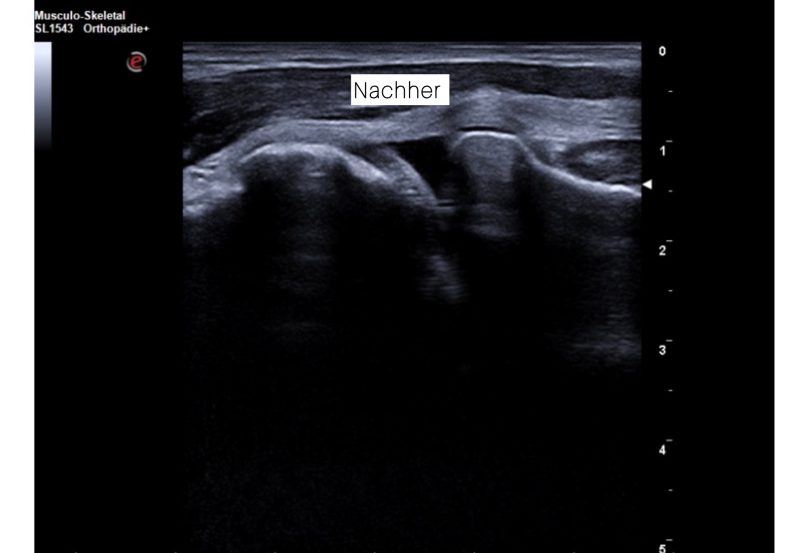

Hier sehen Sie ein weiteres aktuelles (01/26) Ergebnis in unserer Praxis: